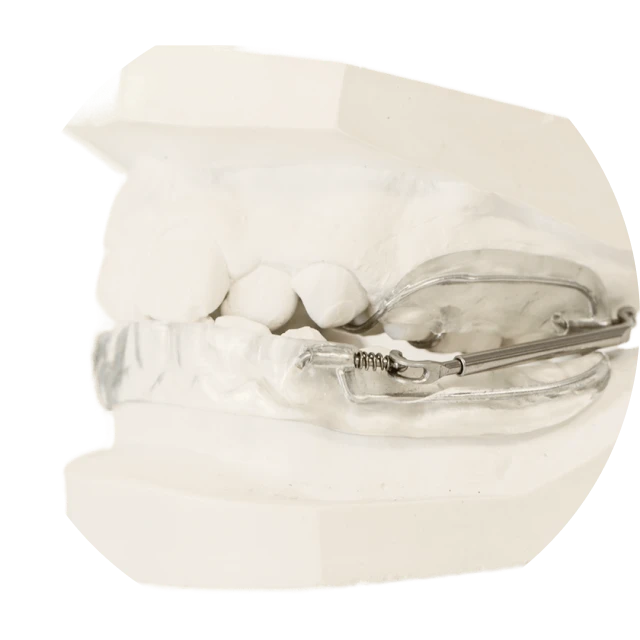

Les traitements interceptifs sont destinés aux jeunes enfants et visent à corriger ou prévenir certaines anomalies dentaires ou fonctionnelles dès leur apparition. En intervenant tôt, ils permettent de guider la croissance des mâchoires, améliorer les fonctions orales (respiration, déglutition, mastication) et faciliter les traitements futurs.